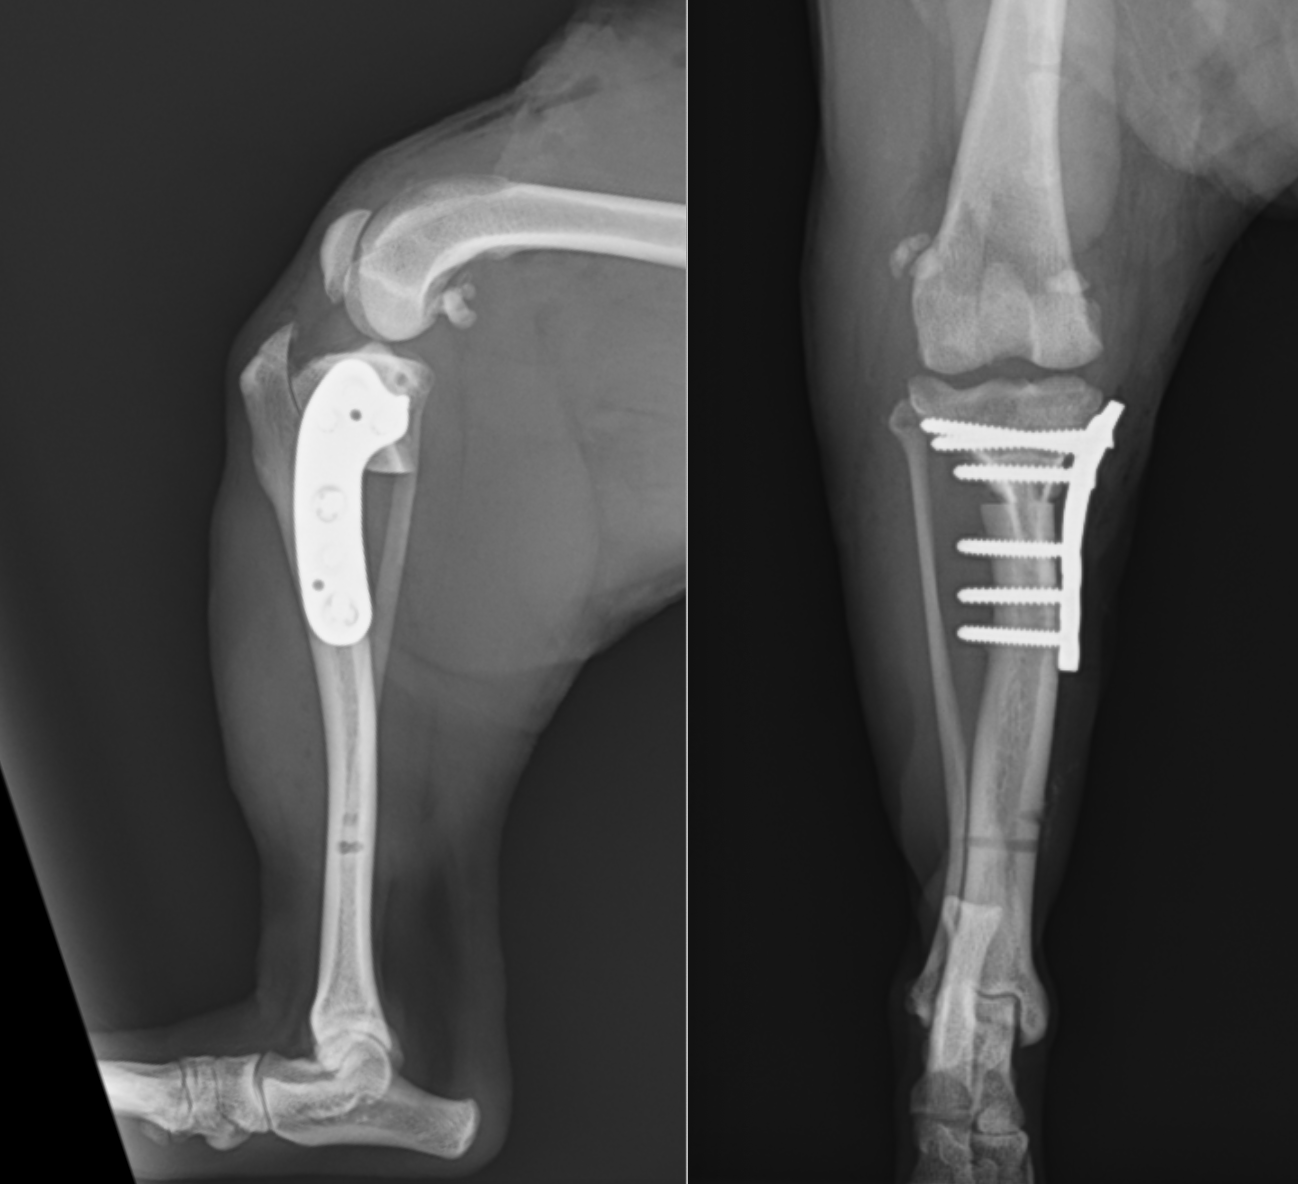

近年では小型犬の前十字靭帯断裂も増えてきています。背景には膝蓋骨内方脱臼によるものが関与していると考えられます。このレントゲンも4kgほどのトイプードルです。

カーブプレートというプレートを用いています。前方の圧迫もかけられる新しいタイプのプレートです。

こちらもカーブプレートです。

2kg代の子にはFixinというプレートを用いることもあります。